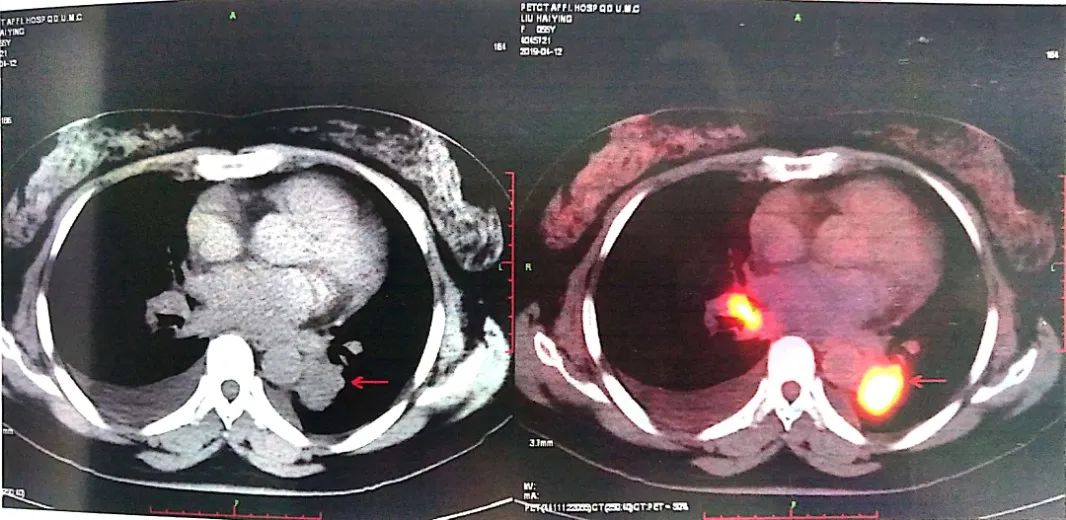

2019-04-12 PET-CT显示①右肺下叶后基底段胸膜下软组织密度肿块(大小26*30mm)。

②左肺下叶纵隔旁软组织密度肿块(大小28*31mm)。

③双肺门、纵隔内隆突下、气管旁、主肺动脉窗、血管前间隙、右侧颈部Ⅴ区及锁骨区多发增大淋巴结。

至此为止,患者的诊断为:肺恶性肿瘤 小细胞癌 广泛期 cT4N3M0 IIIC期(病灶1:右肺下叶,病灶2:左肺下叶),此时先给予标准化疗方案,EP方案:依托泊苷100mg/㎡ d1-3+顺铂75mg/㎡ d1-2 q21d*2。结果如下:

可以看到右肺下叶的病灶有明显缩退,但左肺下叶情况未能改善,因此我们再次在CT引导下左肺占位穿刺活检术。在给予第3周期EP方案化疗方案的同时,进行病理检测,发现理:左下肺病灶为低分化癌,符合腺癌,不除外复合性癌可能。通过肺癌常见基因检测(ARMS法)确定为ALK融合阳性。